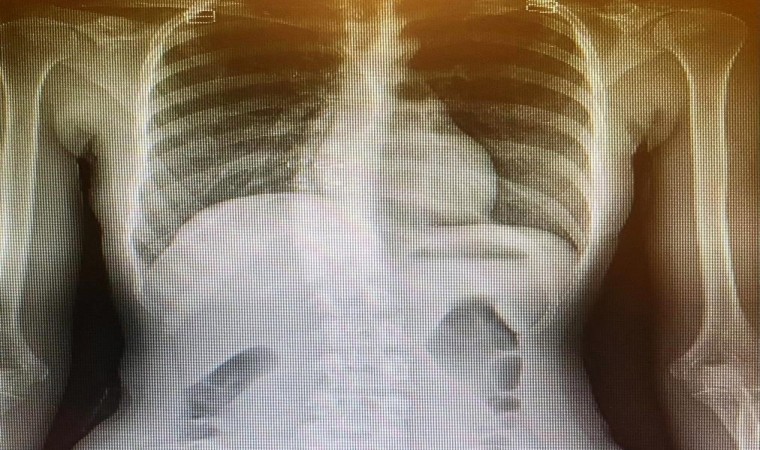

Skolyoza erken tanı koyulmamasının kozmetik problemlerin yanı sıra ciddi sağlık sorunlarına da yol açacağını dile getiren Medicana International Samsun Hastanesi Fizik Tedavi ve Rehabilitasyon Uzmanı Doç. Dr. Dilek Eker Büyükşireci, “Skolyoz büyüme çağındaki çocukların (9-17 yaş) geleceğini tehdit eden önemli bir sağlık problemidir. En sık genç kızlarda, ergenlik çağında, hızlı büyüme döneminde ortaya çıktığından büyüme gelişme cağındaki çocuklarımıza bu açıdan ebeveynler olarak dikkat edilmesi gerekir. Eğer zamanında tespit edilmezse kozmetik problemlerin yanında erişkinlikte bel-sırt ağrıları, kalp ve akciğer sorunları yaşanabilir. Büyüme gelişme cağındaki çocuklara arkadan baktığımızda omuzlar veya kalçaların yükseklikleri eşit değilse, ayakta dururken omurgada bir asimetri görülüyorsa ya da öne eğilirken sırtta hörgüç görünümü oluşuyorsa, çocuklarımız bel, sırt, boyun ağrısı yaşıyorsa anne ve babalarımız çocukta skolyoz olabileceği konusunda uyanık olmalılar. Skolyoz tanısı koyarken fizik muayenenin yanında skolyoz röntgeninden yararlanıyoruz. Skolyoz röntgeninde ‘cobb açısı’ dediğimiz eğrilik açısının 10 derecenin üzerinde olması çocukta skolyoz olduğunu gösterir” dedi.